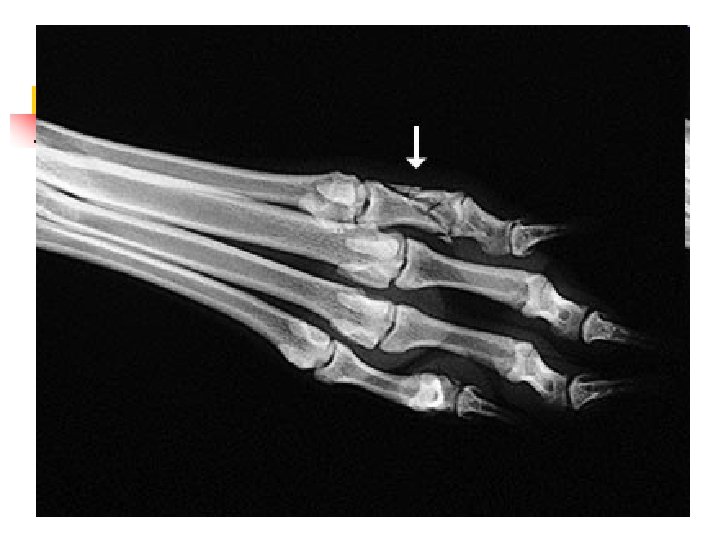

When Animals Limp n n n The good new is that 9 out of 10 limping animals have what we call soft tissue injuries a sprain, a pull, a bruise and only require exercise restriction to heal. However, 1 out of 10 animals with lameness has something more serious, and we can tell which ones by close observation of the patient walking and careful physical examination. In those cases, radiographs are used to make a diagnosis.

Hip Dysplasia n n Hip dysplasia is a looseness in the hip joint. The hip is a ball-and-socket joint and the head (ball) of the femur (thigh bone) normally should be deep within the hip socket. When hip dysplasia is present, the ball moves in and out of the socket with ease. Over time arthritis (degenerative joint disease, osteoarthritis) sets in as the body tries to stabilize the loose joint.